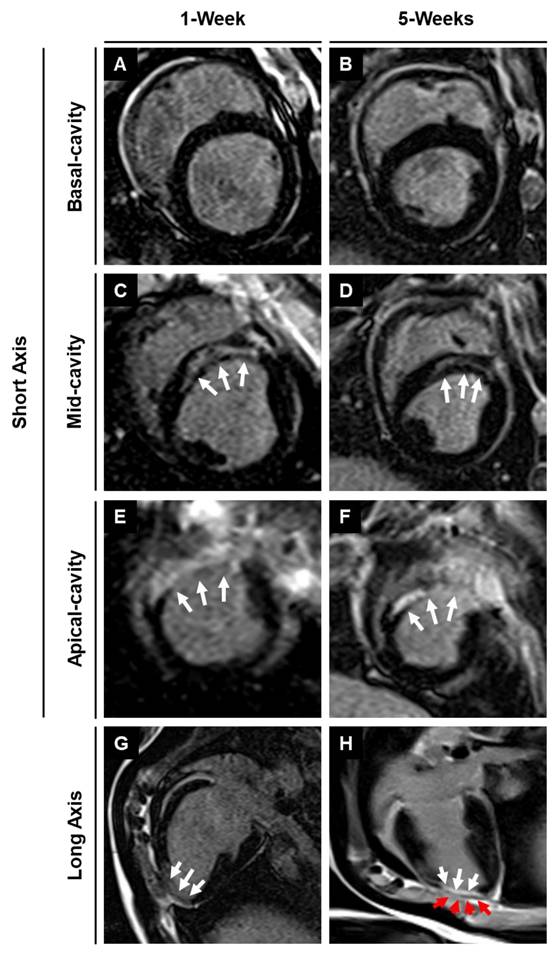

3.5. Assessment of infarction using magnetic resonance imaging with late gadolinium enhancement

Figure 6

MRI-LGE images showing the site of patch transplantation on the pig heart. Representative LGE images along the (A-F) short and (G-H) long axis at 1- and 5-weeks post-MI in MI + Patch group. White arrows are pointing towards the hyper enhanced infarcted region involving the left ventricular apical wall and interventricular septum. Red arrows are pointing towards the transplanted epicardial patch over the infarcted region (dark area on LGE imaging) (H).

Use of translationally relevant preclinical animal models is essential to the successful translation of therapies from bench to bedside[54-56]. The similarity in the size and anatomy of pig hearts with that of human hearts makes them an ideal choice for preclinical studies[54]. However, most of these studies are designed to deliver cell-based therapies immediately after induction of MI, which does not accurately mimic the disease pathology and heterogeneity of MI patients in the clinic[56]. In our study, we developed a translationally relevant porcine model wherein we transplanted the hiPSC-CM-seeded cardiac patch at one-week post-MI to allow sufficient time for the initiation of early cardiac remodeling and initiation of fibrosis, as evidenced by the hyper enhanced region in the LGE images at one-week (Fig. 6). Moreover, the interval between MI induction and cell transplantation increased the heterogeneity in the infarct size among the pigs used in the study (Supplementary Table 2). Recent investigations in mini pigs and non-human primates have demonstrated improved clinical translatability when cell-based therapies are administered after the onset of early or late cardiac remodeling[38, 57, 58]. Therefore, the design and outcomes of our study may provide higher potential for future efficacy studies and translation to clinical trials.